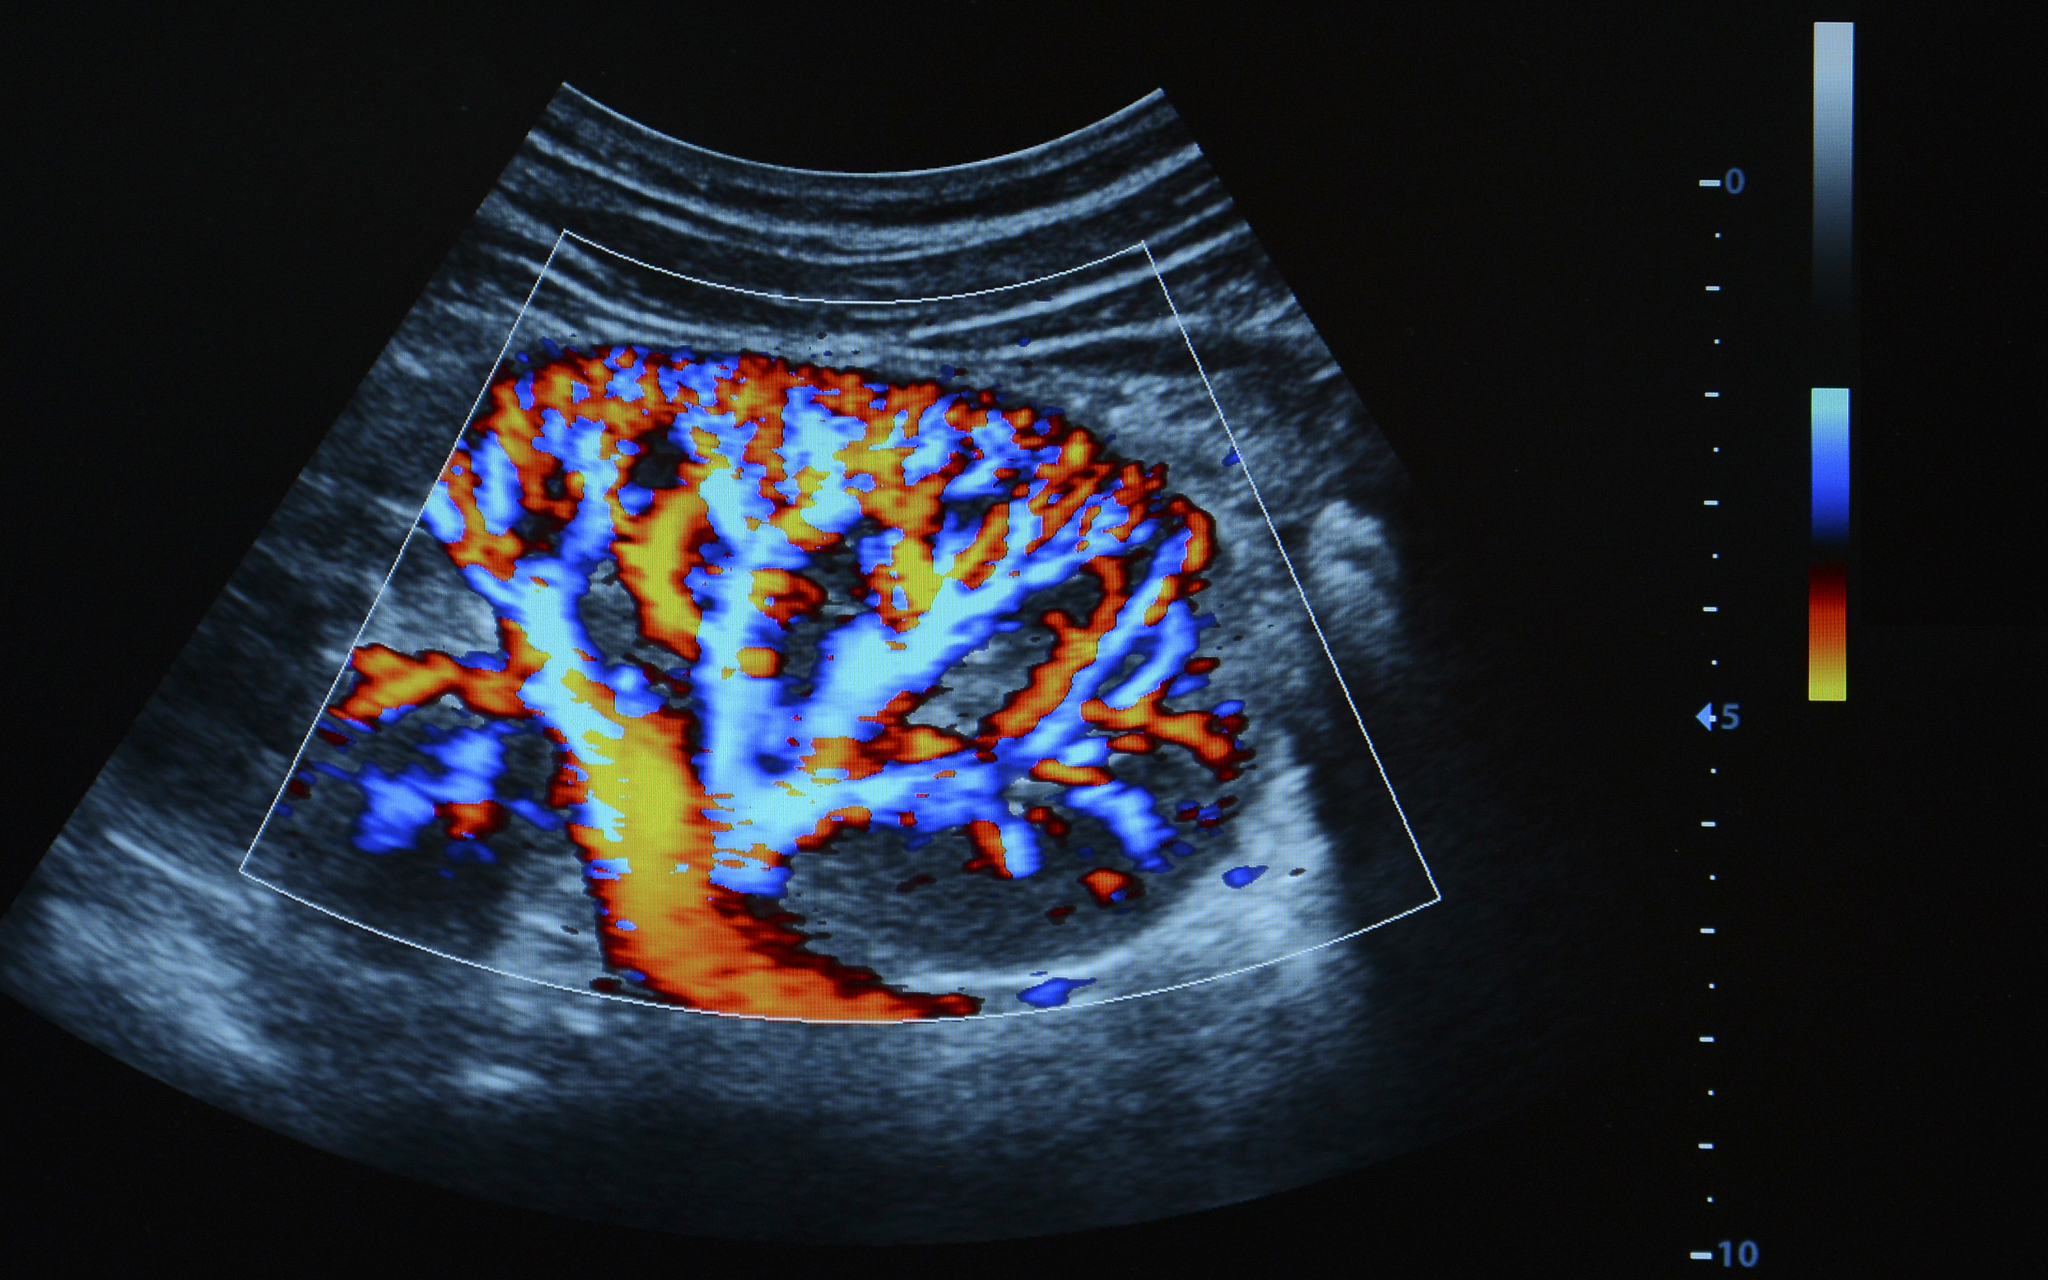

肾细胞癌是一种常见的泌尿系统恶性肿瘤,早期诊断对于提高患者生存率至关重要。超声检查作为一种无创、便捷的影像学检查方法,在肾脏疾病诊断中发挥着重要作用。近年来,人工智能技术的迅速发展为超声图像的分析和应用带来了新的突破,基于超声图像的人工智能技术在肾细胞癌诊断中的应用也取得了显著进展。

人工智能技术,特别是深度学习算法,可以通过学习大量超声图像数据,自动识别和提取图像中的关键特征,从而辅助医生进行肾细胞癌的诊断。其工作原理如下:

1. 数据收集和标注: 收集大量的肾脏超声图像数据,并由经验丰富的医生进行标注,区分正常组织和肿瘤组织。2. 模型训练: 使用标注好的数据训练深度学习模型,使模型能够学习到正常组织和肿瘤组织之间的差异。3. 模型测试和验证: 使用独立的测试数据集评估训练好的模型的性能,包括准确率、灵敏度、特异度等指标。4. 临床应用: 将训练好的模型应用于临床实践,辅助医生对患者的超声图像进行分析,提供诊断建议。